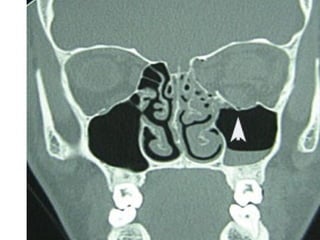

Blowout Fractures of Orbit

• Originally defined as orbital floor fractures

without fracture orbital rim, but with

entrapment one or more soft tissue structures

Blowout Fractures

• Blowout fractures now refer to fractures of the:

–   Orbital floor

–   Medial wall

–   Lateral wall

–   Superior wall

• “pure” blowout fractures – trapdoor rotation to

bone fragments involving central area of bone

• “impure” fracture – fracture line extends to orbital

rim

Radiographic Evaluation

• CT scan of the orbits

• Plain films not useful due to a high rate of

false negatives and non-diagnostic studies